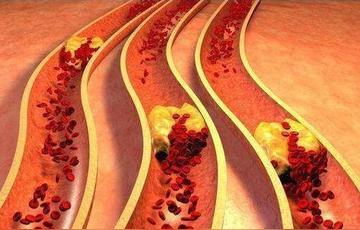

血管一堵死亡風險飆高!3種食物堪稱「天然化栓王」 每天吃一點血管乾淨了「血栓繞道走」